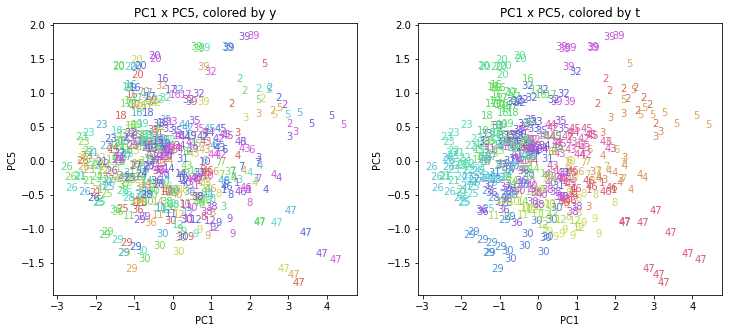

PCAの結果の第n主成分をPCnと表記します。

医療費データの場合と同様に、PCAの結果を見やすく表示するため、seabornのカラーパレットを使って、年月別、都道府県別に色分けして図示してみます(左側が年月別に色分け、右側が都道府県別に色分け)。PC1~PC8まで表示しました。

都道府県番号の表示

上の色分けだけでは都道府県が区別しにくいので、医療費データの場合と同様に、点の代わりに都道府県番号をプロットした図も描いておきます(色分けは上と同じ)。

医療費データの場合ほどはっきりとはしていませんが、PC2が概ね時間の経過を表す成分で、残りの成分が時点によって変わらない地域の特徴を表す成分となっているようです。

また、PC1×PC3を見ると、47沖縄が他の都道府県からかなり離れたところに位置しており、沖縄の地域差が際立っているのが分かります。これは、以前別の記事で年齢階級のない健診データでPCAを実行した場合と似た結果となっています。